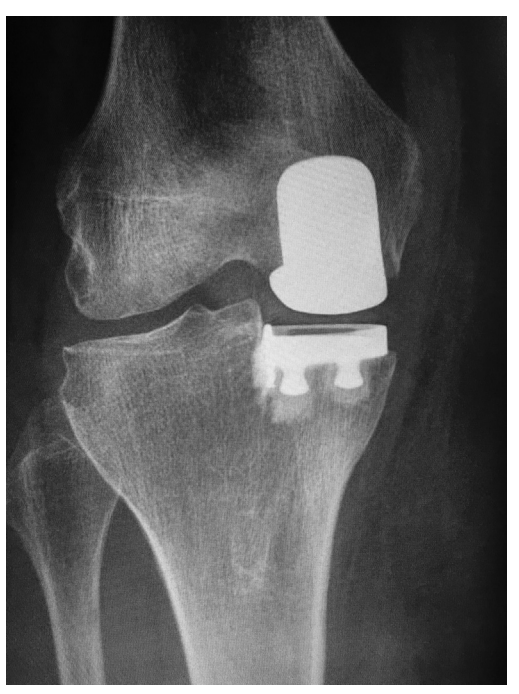

胫骨内侧塌陷(图7)或骨折是UKA术后罕见的并发症,仅占UKA失败翻修的2%。这些骨折可能与假体对齐以及手术技术有关。冠状位对内翻或任何外翻均较大的胫骨内翻会显著增加胫骨近端内侧的负荷。这些骨折的治疗可包括切开复位内固定或翻修TKA,这取决于骨折组件的稳定性和骨折大小。

图7:X线片显示胫骨内侧塌陷。

UKA至TKA的翻修被认为是一种相对简单的手术,可能比原发TKA的翻修更有优势。然而,UKA至TKA的翻修通常比原发TKA更具挑战性,大约50%的患者会有明显的骨缺损,33%的病例需要加强固定。UKA失效的模式影响修正的复杂性,但大多数UKA修正可以使用主要组件成功完成(图8),胫骨塌陷的翻修具有最高的复杂性(图9),因为这些病例将更频繁地需要增加和约束。

图8:从以前的UKA翻修到TKA后的术后主要成分X线片。

图9:由于内侧塌陷导致UKA翻修失败后的术后X线片。